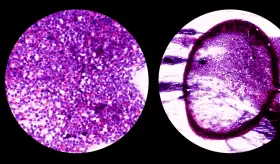

Hay diferentes tipos de linfomas dependiendo del tipo de célula linfática afectada. El linfoma tipo Hodgkin puede aparecer a cualquier edad, afecta más a hombres que mujeres y la mayoría se curarán completamente